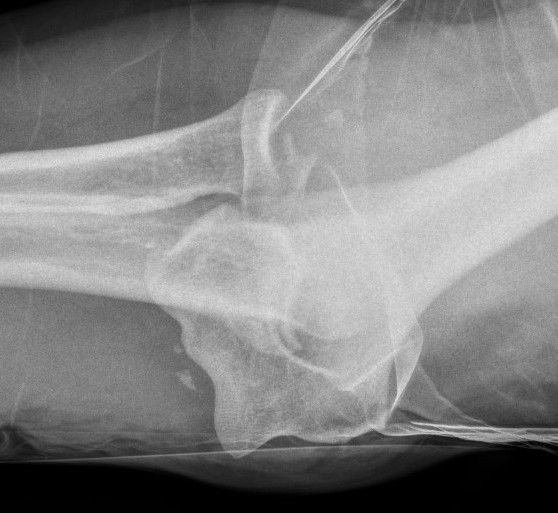

Overstuffing

| Lesser sigmoid notch | Symmetry of ulnohumeral joint |

|---|---|

|

Radial head shoulder articulate with lesser notch

Ensure no gapping of lateral ulnohumeral joint |

![]() |

- cadaveric study

- increased medial ulno-humeral joint line gapping with overlengthening of 6 or 8 mm

- increased lateral ulno-humeral joint line gapping with overlengthening of 2 mm